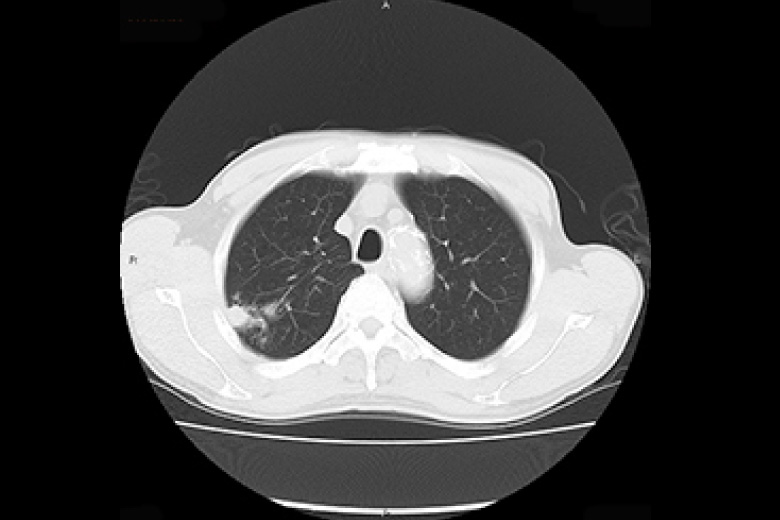

X線CT

2台のマルチスライスCT(320列、64列)にて検査を行っております。

CTはX線管と検出器が体の周りを360°回転しコンピュータ処理により画像を作成します。

頭部・胸部・腹部・四肢など全身の撮影ができ、心臓(冠動脈)などの撮影も可能です。

320列CTにより全身をより短時間で撮影できるようになり、患者さんの負担が少なくなりました。また、320列CTでは16cmの範囲(頭部や心臓など)を1回転で撮影できます。

また逐次近似再構成により被ばくの少ない検査が受けられます。

肺腫瘍